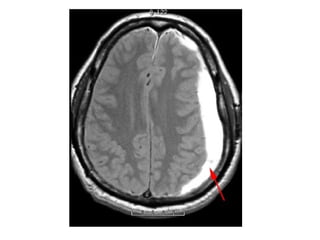

*MRI :

-Absence of flow void , thrombus is visualized on

MRI as loss of the normal venous flow void on

T2

-The clot acutely is isointense on T1 and

hypointense on T2 (this can mimic a flow void)

, with subacute clot becoming hyperintense

on T1